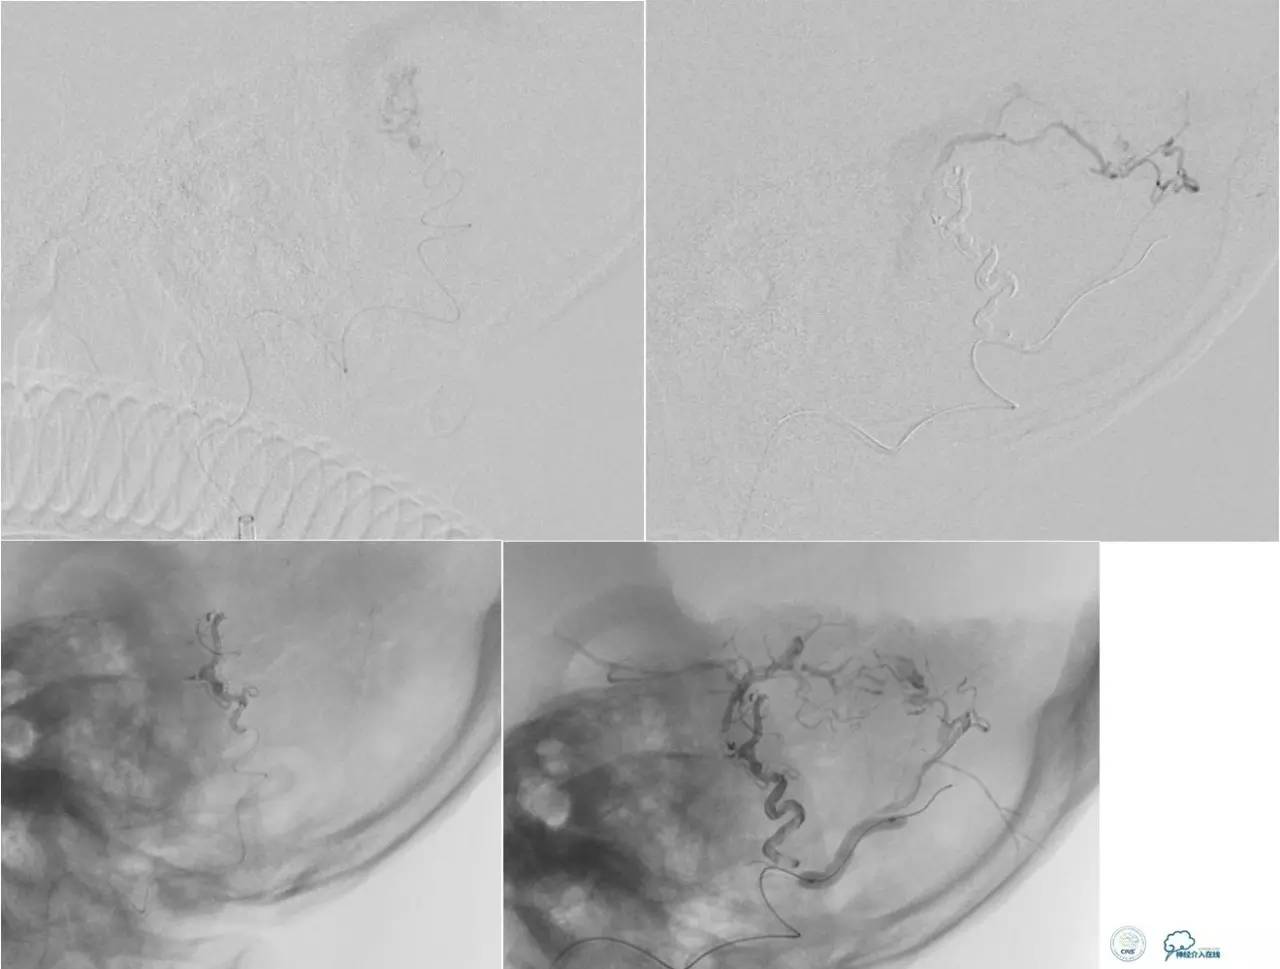

高流量的瘘充盈球囊,降低供血动脉内的血流量,防止胶提前进入静脉端。

球囊闭塞超选血管远端动脉,增加超选动脉血流量,利于胶向瘘口弥散。